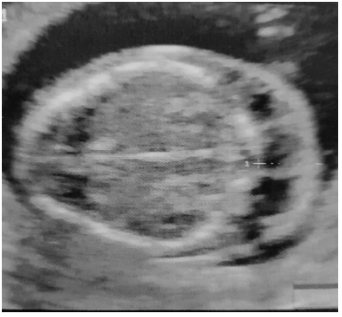

Uma primigesta de 21 anos de idade, com dezenove semanas e sem antecedentes mórbidos, realizou uma ultrassonografia morfológica, que apresentou, isoladamente, a malformação ilustrada a seguir.

Enunciado 3511079-1

Com base nesse caso hipotético, assinale a alternativa correta.